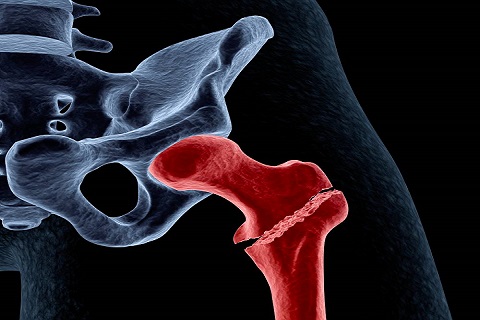

Fracturas óseas

Una fractura produce una ruptura parcial o completa en la continuidad del hueso.